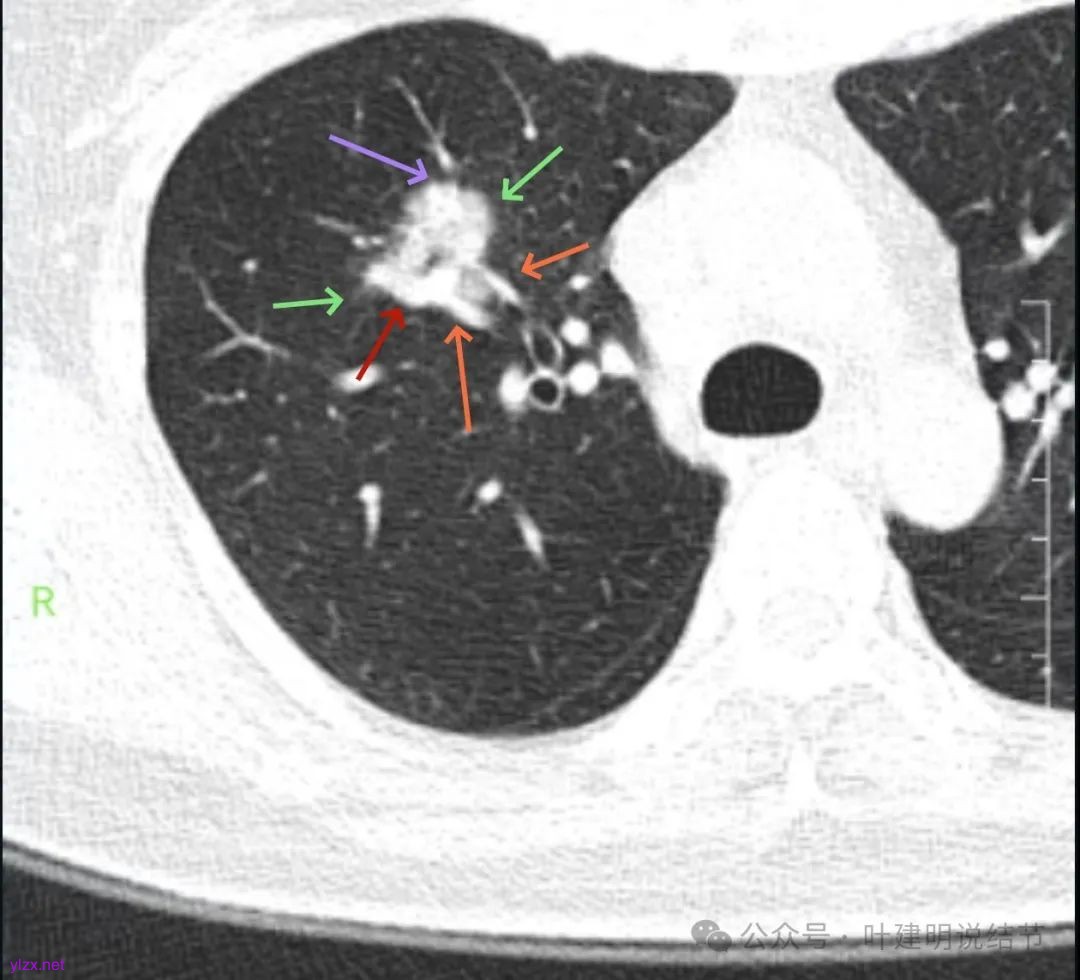

影像展示与分析:

你的右上叶这个病灶基本上肯定是肺癌,要尽快处理。从影像上看有以下特点:1、整体轮廓清楚,不似普通炎症的周围有晕或阻塞性改变;2、边缘明显的浅分叶,总体上的感觉膨胀性明显,不管哪个层面看上去都是鼓鼓的;3、边缘区域有磨玻璃成分而且也是分叶状的;4、部分层面见血管进入;5、空腔病灶的壁厚薄不均,内壁不光滑。我考虑中低分化肺癌,由于腔静脉旁有明显肿大淋巴结,需要进一步完善增强CT以及PET-CT检查以明确有无远处转移,是否仍可手术治疗(从病灶本身来说是可以肺叶切除治疗的)。要尽快处理。意见供参考!